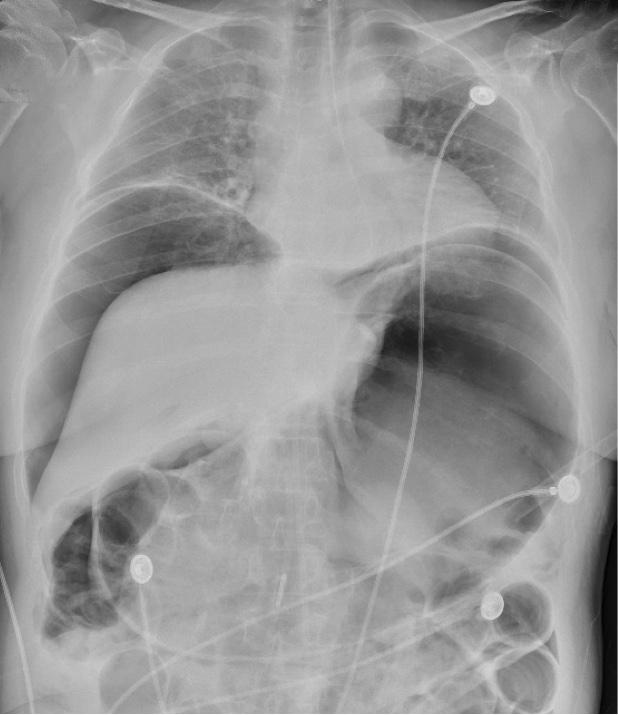

A 53 yo female presents with acute onset of sharp abdominal pain. She is rolling back and forth on the stretcher, visibly in pain. She has tachycardia, but otherwise her vitals are normal. A stat portable x-ray is shown below. What's the diagnosis? (scroll down for answer)

Answer: pneumoperitoneum

- Requires emergent surgical consultation and broad spectrum antibiotics to cover enteric organisms; metronidazole or a carbapenem may be added to the traditional two-antibiotic regimen

- In rare cases abdominal compartment syndrome may ensue if the perforation acts as a one-way valve creating a tension pneumoperitoneum